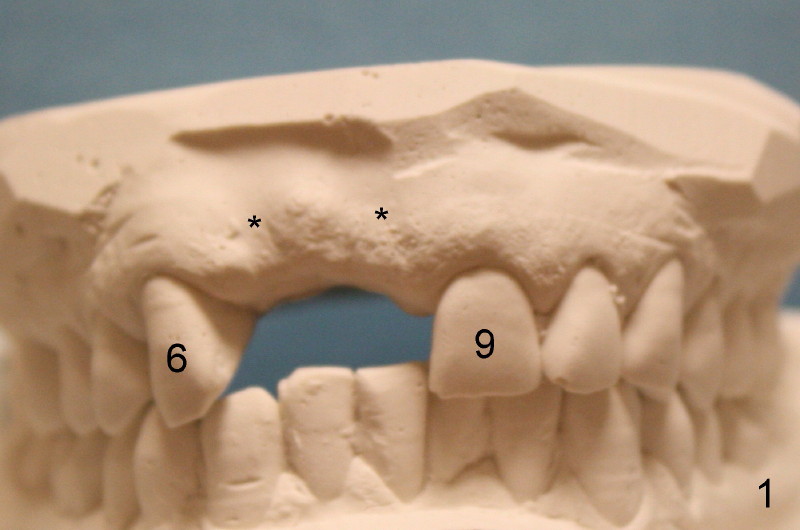

Forty-five-year-old Spanish man has lost the teeth #7 and 8 for 2 years (due to caries, Fig.1,2) with localized buccal plate atrophy (Fig.1-3 *).  Wax-up (Fig.4) shows that implant supported crowns will look longer than their counterparts (#7,8 vs. 9,10).

CBCT with surgical stent shows that it is possible to place 4x17 and 4.5x17 tapered implants for the sites #7 and 8 with bone expansion, respectively (Fig.5 coronal section, Fig.6 axial (at the level of 16.4 mm line in Fig.5), Fig.7, 8 sagittal across the site #7 and 8, respectively).